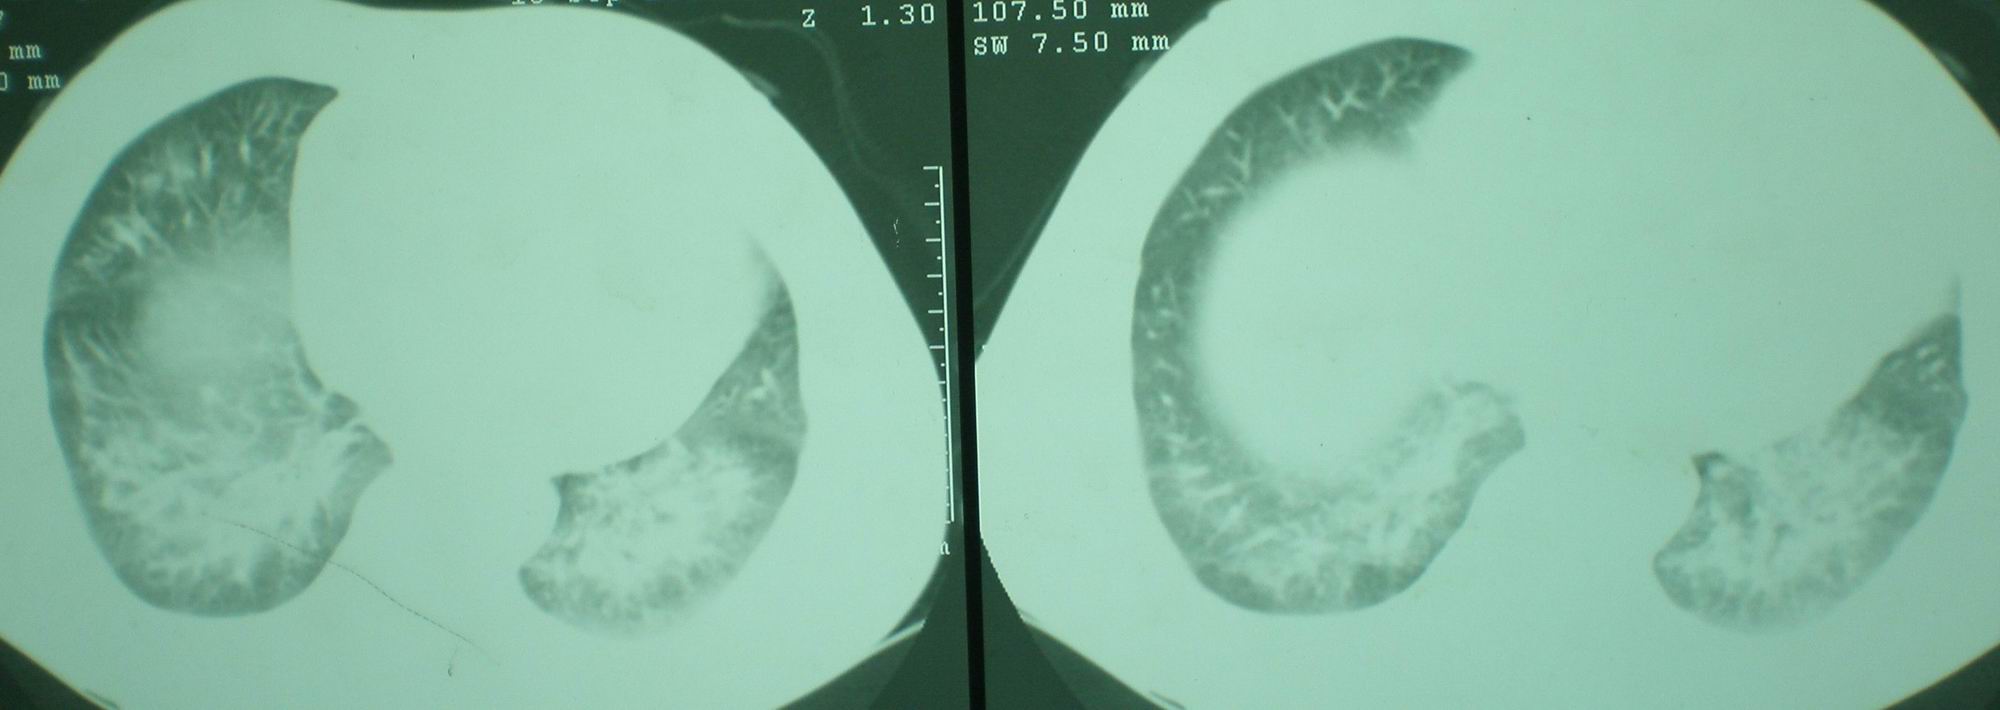

2008年9月18日ct片